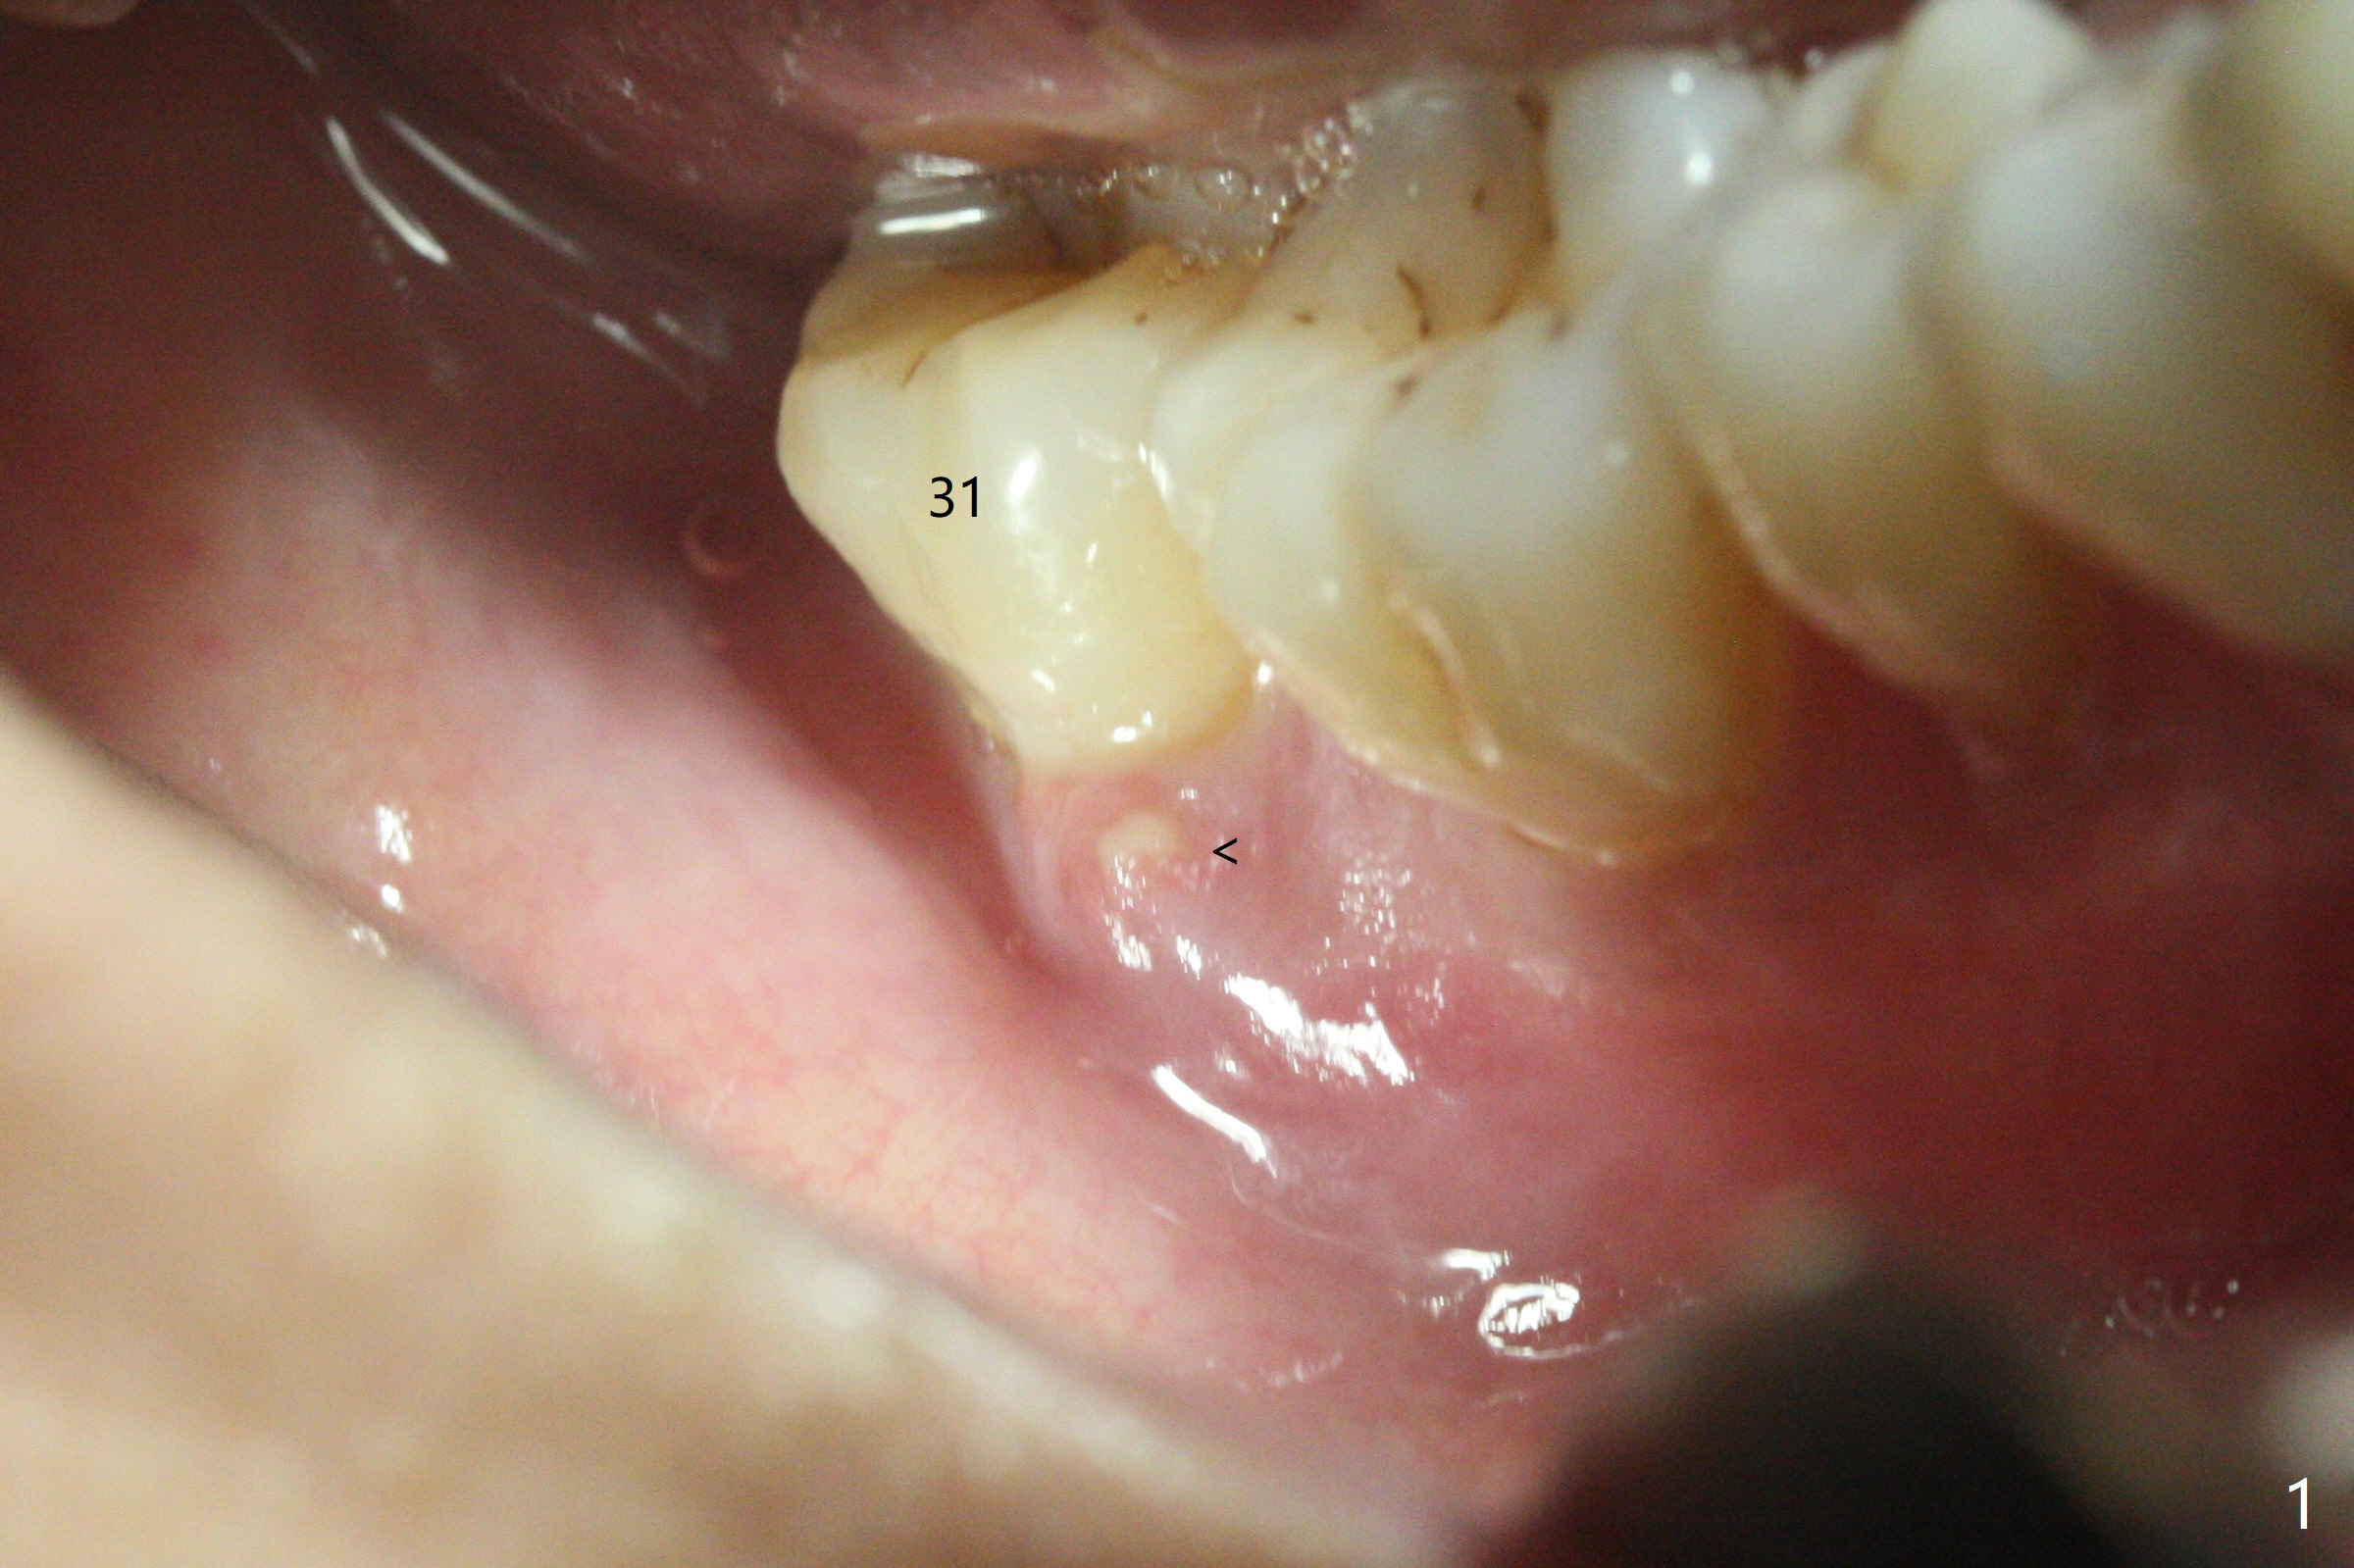

31号牙拔除前近中颊侧有一个瘘道(图一:<),说明32号牙被感染可能性小。术中发现虽然一小部分智齿牙冠与第二磨牙巨大牙槽窝相通(图二:*),但是病变并没有往智齿周围发展(S(可能是牙囊));借助导板(9毫米offset)毫无困难完成钻洞,但是嫌钻洞深度不够。由于植体扭力低(<10 Ncm),只好放置粘性骨粉(图三),覆盖PRF和Cytoplast,PTFE缝线,以及树脂敷料。病人左下第二磨牙缺失多年,牙槽嵴粘膜出现白色病变(图四:箭头),可能与对合磨牙延申有关(图五:箭头)。如果这个牙位需要导板植牙,垂直距离将是一个严峻问题。即种导板(图六:31)与延期导板(18)金属圈放置有不同,相差1.5毫米(图七):即种(由于拔牙)金属圈可以放低,而愈合牙位(由于牙龈存在)金属圈必须放高。所以第二磨牙即种有足够垂直空间优势。术后一周复诊,老的树脂敷料不牢(因为下面没有基台),脱落,下面不可吸收膜没有外翻,重新制作敷料(图八:A)。术后一个月由于2,3号牙之间牙周炎发作,树脂敷料牢靠,下面不可吸收膜稍微暴露,两者取出后,植体略微暴露。没有基台,骨粉固定好像不佳。